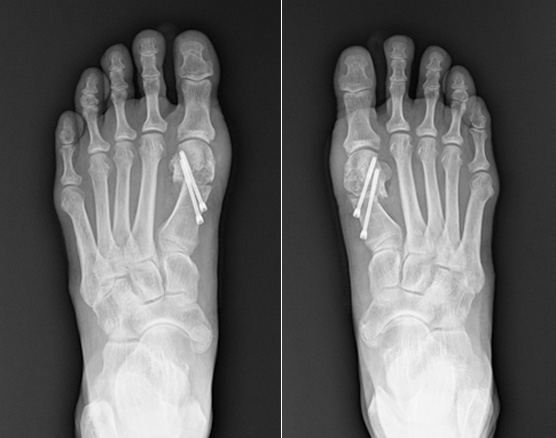

MICA, minimally invasive Chevron & Akin osteotomy

이전에는 무지외반 수술은 5cm 이상 피부를 절개하고 뼈를 싸고 있는 골막을 절개하여 수술을 하였습니다.

그래서 무지외반 수술은 통증이 심한 수술에 속하였지만

비절개 무지외반 교정술을 시행하고 나서는 획기적으로 회복 속도가 빨라졌고,

골막을 절개하지 않기 때문에 수술 후 통증도 많이 줄었습니다.

비절개 무지외반 교정술은 나사와 절골침이 들어갈 정도의 작은 구멍만 내고 하는 수술로 흉터는 낫고 나서는

거의 점처럼 보입니다. 수술 다음 날부터 큰 통증 없이 딛고 걸어 다니는 것도 가능합니다.